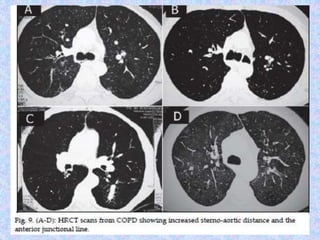

CT finding in emphysema is diagnosed by alveolar septal destruction and

airspace enlargement, which may occur in a variety of distributions.

Centrilobular emphysema is predominantly seen in the upper lobes with

panlobular emphysema predominating in the lower lobes. Paraseptal

emphysema tends to occur near lung fissures and pleura. Formation of giant

bullae may lead to compression of mediastinal structures, while rupture of

pleural blebs may produce spontaneous pneumothorax /

pneumomediastinum.

Abnormal chest X-rayfindings are usually not seen until COPD is severe. In this case, the X-ray may show: Flattening of the diaphragm, the large muscle that separates the lungs and heart from the abdominal cavity. Increased size of the chest, as measured from front to back. A long narrow heart. Abnormal air collections within the lung (focal bullae). On the lateral radiograph, a "barrel chest" with widened anterior-posterior diameter may be visualized. The "saber-sheath trachea" sign refers to marked coronal narrowing of the intrathoracic trachea (frontal view) with concomitant sagittal widening (lateral view). CT finding in emphysema is diagnosed by alveolar septal destruction and airspace enlargement, which may occur in a variety of distributions. Centrilobular emphysema is predominantly seen in the upper lobes with panlobular emphysema predominating in the lower lobes. Paraseptal emphysema tends to occur near lung fissures and pleura. Formation of giant bullae may lead to compression of mediastinal structures, while rupture of pleural blebs may produce spontaneous pneumothorax / pneumomediastinum.